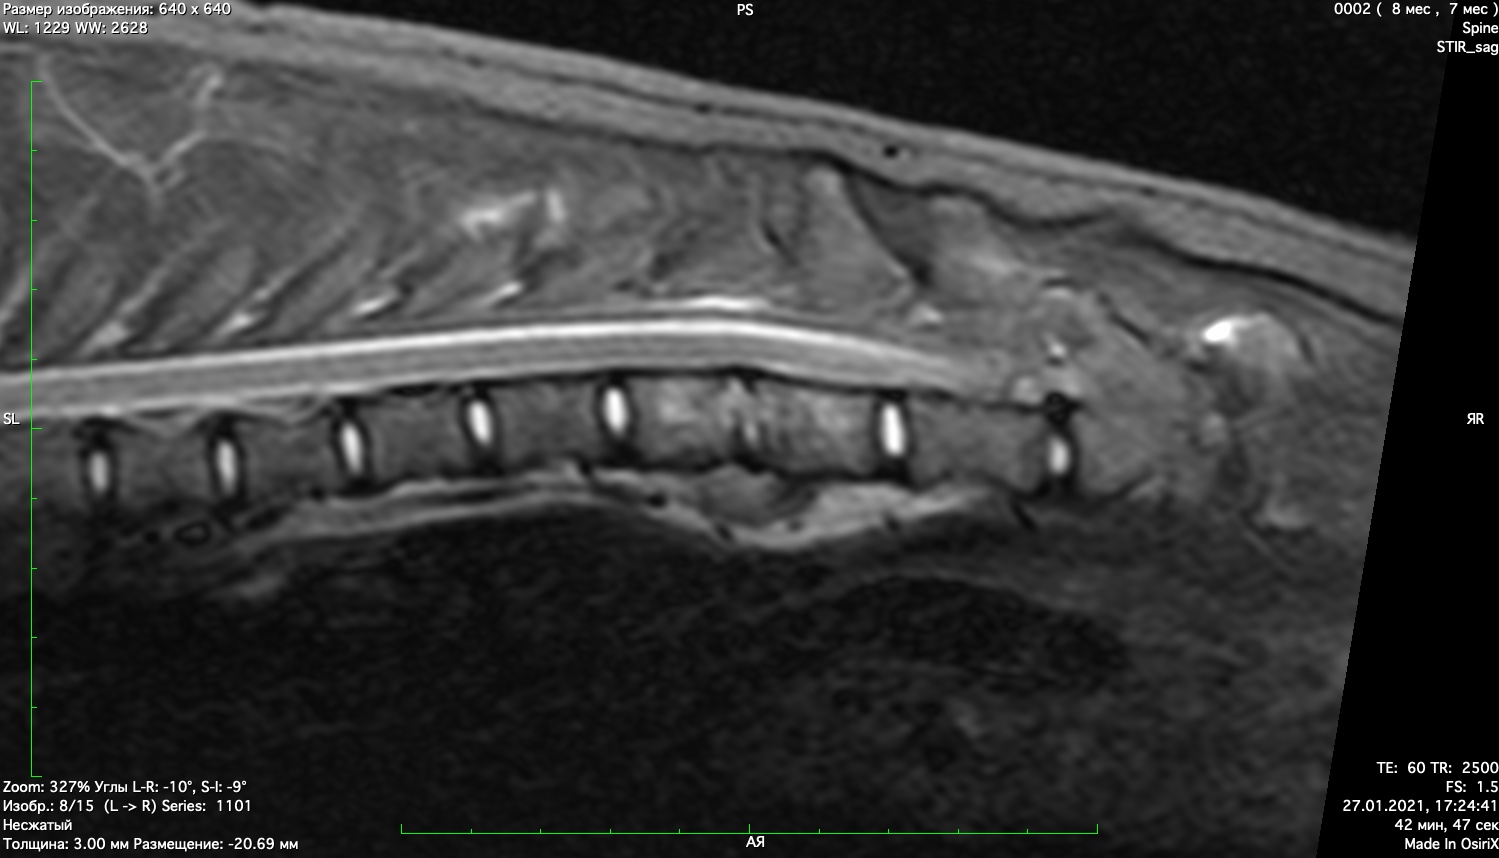

При проведении неврологического осмотра установлено- неврологический дефицит отсутствует, сильная болезненность при пальпации поясничного отдела позвоночника При проведении мрт диагностики установлено признаки воспаления позвонков поставлен диагноз-дискоспондиллит. начато лечение дискоспондиллита -антибиотиками